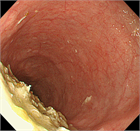

1. アカラシアの内視鏡所見について追加記載を行った。

1. 食道アカラシアの診断は食道内圧測定であるHRM(high-resolution manometry)で行う。

1. HRMに加えて、食道バリウム造影で経時的に食道内のバリウム貯留の程度を評価するTimed barium esophagogram(TBE)は診断に有用である。